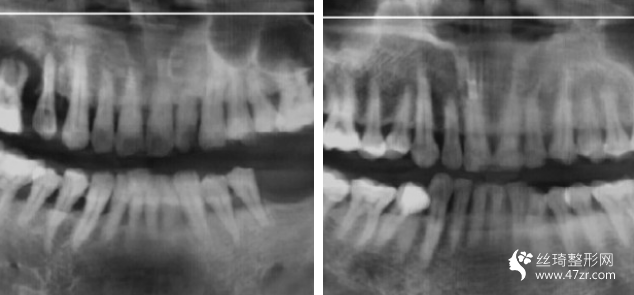

3.長(zhǎng)沙優(yōu)享新天地口腔門(mén)診部張思齊執(zhí)業(yè)醫(yī)師案例展示

這種植牙終于完全好了,特別開(kāi)心,試著吃一些軟食物,我已經(jīng)很久沒(méi)有用左邊咀嚼過(guò)東西了,過(guò)程不疼的!麻藥打好!半個(gè)小時(shí)就好了!今年年頭裝的牙!用到現(xiàn)在了!很牢固!植入種植體,修復(fù)一段時(shí)間就可以戴牙冠了